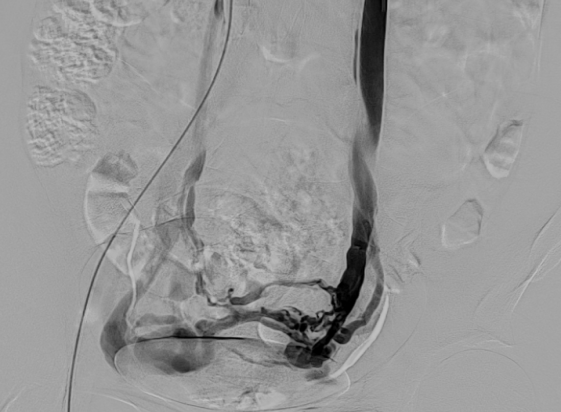

3.经皮导管逆行卵巢静脉造影术

目前认为是盆腔淤血综合征诊断金标准。

盆腔淤血综合征的介入治疗是在局部麻醉状态下,通过股静脉穿刺或颈静脉,引入导丝、导管,插入到盆腔静脉,进行盆腔静脉造影及予以硬化剂、金属弹簧圈等予以栓塞,将有病变扩张的盆腔静脉进行封闭,从而达到治疗的目的。